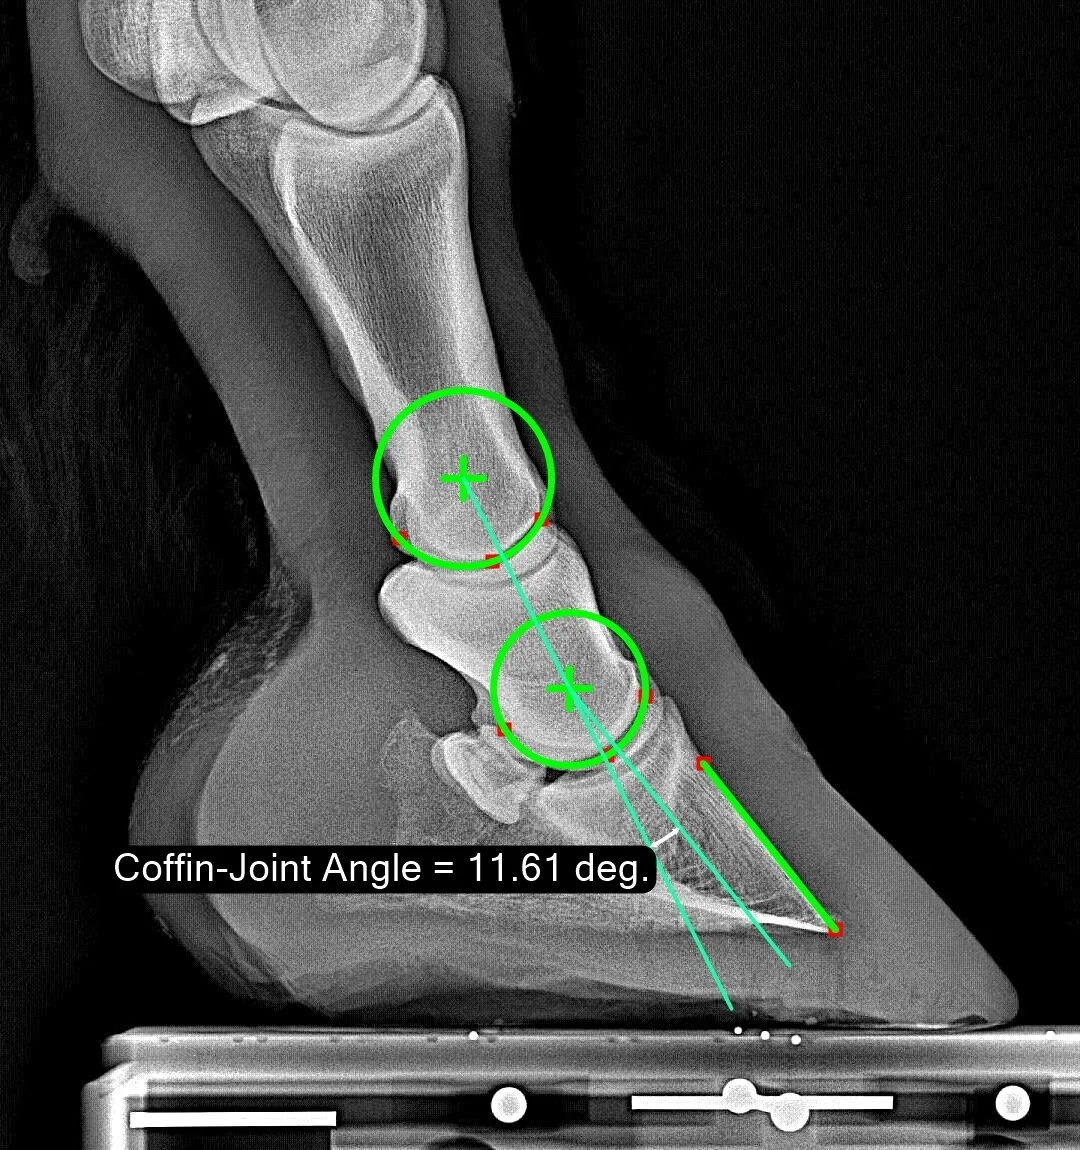

Coffin-Joint Angle

The Coffin-Joint Angle measures the angulation between the P2 and P3 bones. To be precise, it is measured as follows: construct a line connecting the rotation centers of the pastern and coffin joints. Then measure the angular difference between that line and the parietal surface of P3. The details are discussed in this publication. To repeatably quantify a given leg/hoof, it is important to stand the horse with cannon bone approximately vertical when imaging.

Normal Range

The observed normal range is from 2 degrees to 18.5 degrees with a median of 10.5 degrees. This means it is normal (in our population) to be ‘broken back’ by about 10 degrees. Therefore, the angulation shown in this sample image is very close to the median. The larger the value, the more ‘upright’ the pastern.